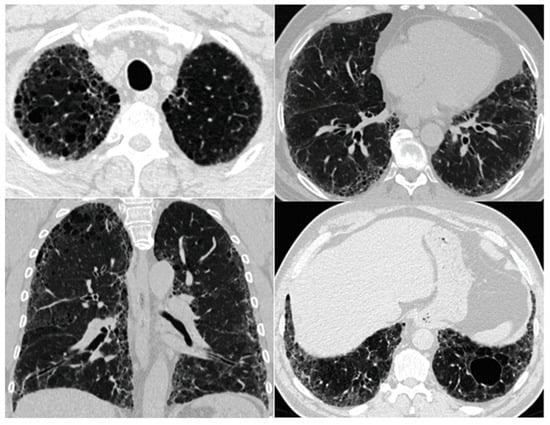

7. Lung Function

| Imaging | Centrilobular and/or bullous emphysema | Coexistence of paraseptal emphysema in the upper zones of the lungs and the UIP/NSIP/DIP in the lower zones, thick-walled cysts in the area of fibrosis | UIP pattern |